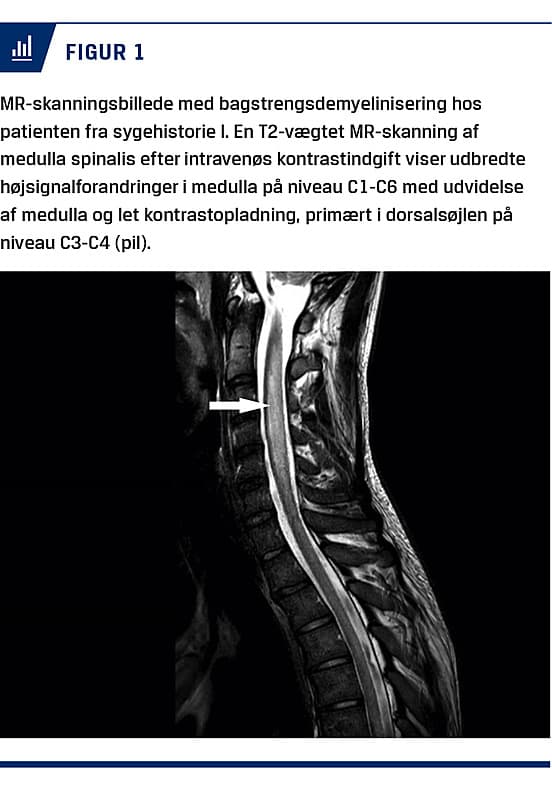

Man fandt megaloblastær anæmi, og han blev diagnosticeret med toksisk bagstrengsmyelopati og polyneuropati som følge af stort lattergasmisbrug (Figur 1 og Tabel 1).

I samråd med Giftlinjen blev der behandlet med B12-vitamin, thiamin og methionin. Forsøgsvis fik han methylprednisolon mod inflammation i rygmarven, men med usikker effekt. Efter fire ugers indlæggelse blev han udskrevet til yderligere genoptræning på en specialinstitution. Ved klinisk kontrol efter fire måneder havde han selvstændig gangfunktion med bilateral dropfodsskinne og op til 500 meters gangfunktion uden støtte. Ved længere afstande anvendte han rollator. Han var fortsat i behandling med clonazepam til udtrapning af misbrug og blev fulgt ved et misbrugscenter.